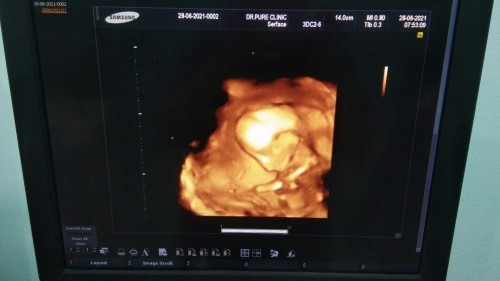

อัลตราซาวด์ ตอนอายุครรภ์ 18 สัปดาห์ น้องเป็น ผู้หญิงค่ะ

พึ่งไปอัลตราซาวด์มาค่ะ แต่น้องนั่งก้มหน้าตลอดเลย เลยได้ภาพมุมนี้มา พอจะดูออกมั้ยค่ะ ว่า น้องมีดั้งหรือป่าว แม่กลัวน้องจะ ไม่มีดั้งเหมือนคุณแม่ค่ะ อิอิ แต่น้องแข็งแรงดี แม่ก็ดีใจค่ะ

น้องยังมีการเปลี่ยนแปลงอยู่ค่ะ รอให้อายุครรภ์เยอะกว่านี้ค่ะจะได้เห็นชัดเจนยิ่งขึ้นค่ะ ถ้าคุณพ่อคุณแม่มีดั้ง ไม่ต้องห่วงว่าน้องจะไม่มีดั้งค่ะ เป็นไปตามกรรมพันธุ์ค่ะ